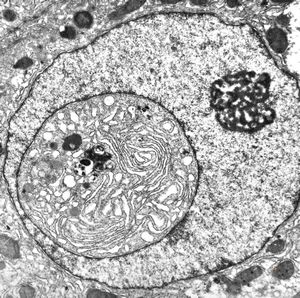

F,61y. | intranuclear cytoplasmic inclusion - giant cell hepatitis